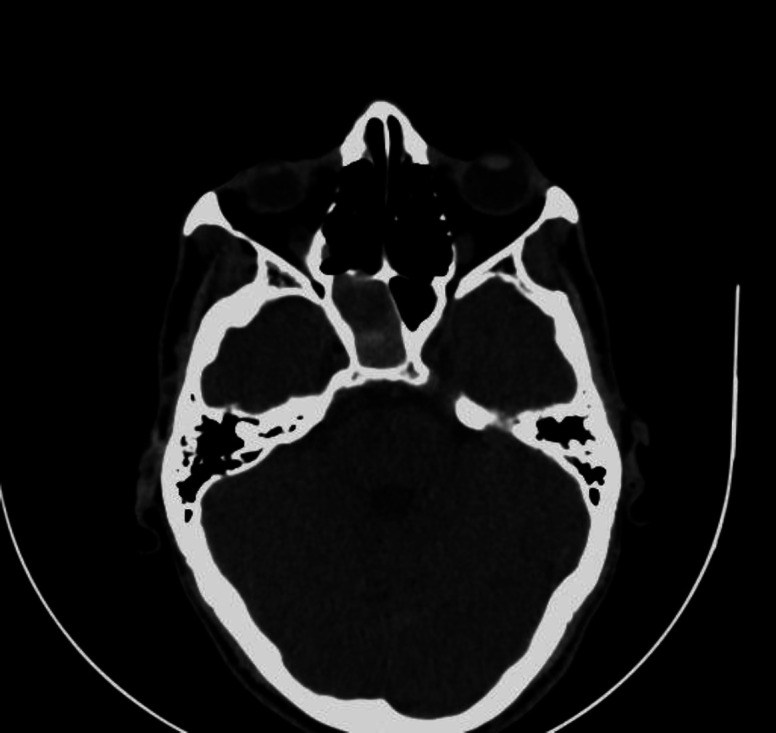

Case report: We report a case of a 57- year old male presenting with recurrent episodes of epistaxis. Contrast-enhanced Computed Tomography of the Paranasal Sinuses and Magnetic Resonance Imaging were performed, which showed a focal defect in the posterolateral wall of the sphenoid sinus through which an aneurysm from the cavernous segment of the Internal Carotid artery was seen herniating into the sinus with an associated hematoma.